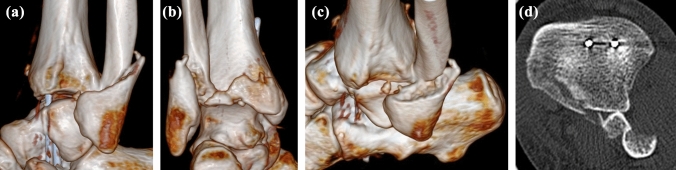

Fig. 3.

CT imaging demonstrated posterior displacement of the proximal fibular fragment fracture behind the distal tibia and a minimally displaced fracture of the posterior malleolus (Bartoníček-Rammelt type 3, two-part fracture with extension into the medial malleolus). a lateral 3D CT view; b posterior 3D CT view; c lateral 3D CT view; d axial CT scan